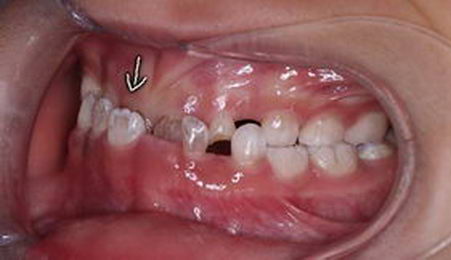

左图为4.5岁,右图为5岁,都是乳牙期间的地包天,即上面的门牙在下面门牙的内侧,会觉得孩子有一个明显的下颌前伸的动作,常伴随面中部的凹陷,容易下唇外翻,造成一定的面型发育问题。那么地包天是怎么形成的呢?

当48岁的父亲的牙齿是地包天时,他的两个儿子均有表现出前牙覆盖浅,前牙反合的倾向,女儿的咬合虽然相对较好,但前牙覆盖仍然偏小。地包天有着非常大的遗传性,暨如果爸爸妈妈是地包天,孩子出现地包天的几率非常大。那如果出现乳牙地包天后我们不管它,随着生长会变成什么样呢?等到12岁后,就容易出现下面的这些咬合变化。地包天会随着孩子长大,越长越差,越发严重。

等到12-18岁换完牙后再出现以上这些复杂的地包天时,往往就需要拔牙矫正,或者需要等到成年后做正颌手术了,孩子吃的苦头也不言而喻了。